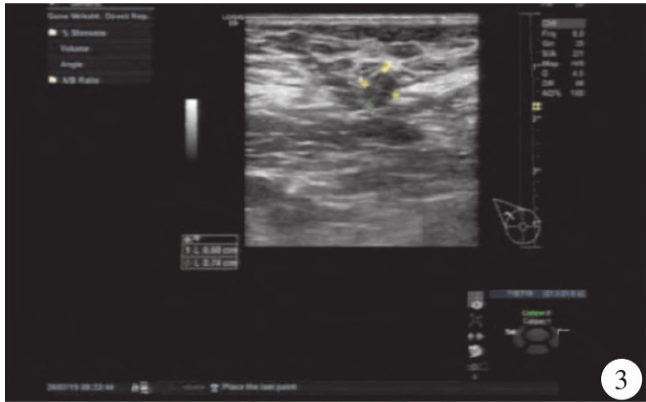

超声检查:右乳腺见大小约3.0cm×1.8 cm×2.4 cm的低回声结节,边界不清,形态不规则,呈角样改变,内见微钙化,弹性成像组织显示蓝色(图1),CDFI显示右乳腺低回声结节内见星点样血流信号(图2);右侧腋窝见约1.4cm×1.1 cm的淋巴结,门结构显示不清,右侧腋窝淋巴结内均见少许星点样血流信号(图3),诊断右乳腺BI-RADS 4c类结节,右侧腋窝异常肿大淋巴结。MRI显示右乳腺外上象限可见结节样稍长T1、稍短T2结节影,边界不清,呈毛刺状,病灶大小约2.1 cm×2.5 cm×2.1 cm,增强扫描呈环形强化(图4、5)。

图2 右乳腺结节内见星点状血流信号显示。